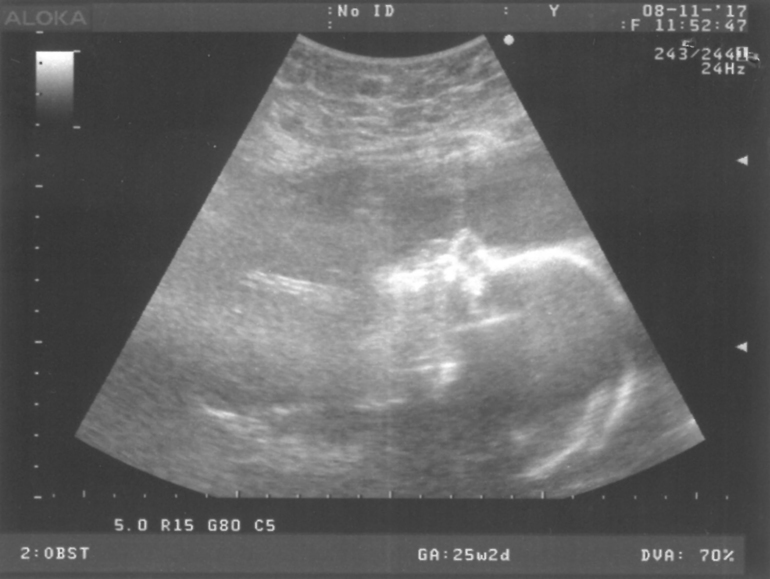

Что имеем на сегодня... Ходили 8 ноября на узи, я записана была на завтра вообще, но пару дней что-то плохо слышала шевеления совсем, забеспокоились, и пошли раньше, смотреть кровотоки, шейку, что всё закрыто. Хотя самое интересное, что как только панику подняли и записались, в тот же вечер доча снова стала ощутимо клёво пихаться)) Ну так вот, пошли, по всему тому за что переживания - малышка на попу села, шейка, плацента всё хорошо, но зато снова разница по сроку, почти на 2 недели меньше. По месячным 25 и 2 дня было, а по узи намеряли 23 и 4 дня. Хотя в 21 неделю на плановом узи было уже почти ровно, только 2 дня разница была. Видимо бронхит мой не прошел даром, малышка мелкая, сказала узистка надо докармливать и посоветовала не ждать планового приема, а идти раньше к врачу, мол или капельницы назначат, или витамины. Написала маловесный плод. Ну и помчалась я на следующий день к врачу, к своей не попала, к другой. ну и говорит она, мол выписываю направление в стационар, там еще перепроверят, может и норм вес, по узи мол это не точно видно, прога рассчитывает по размерам головы, бедра и тд примерный вес. Я в больницу естественно не хочу, попросила витамины пока назначить просто, потому что всё остальное у меня хорошо, на кресле норм всё, по анализам норм, а вес хорошо набирают детки от витамин знаю, которая мне моя гиня не назначает всю беременность... Ладно раньше, но сейчас-то после болезни могла бы. Назначили Элевит, и зачем то Пентоксифиллин.. Спросила зачем второе, говорит мол для кровотоков... Нафига? Если с плацентой и кровотоками у меня всё хорошо на узи было, проверили ж. Не стала пить.

Любимая головешечка))))